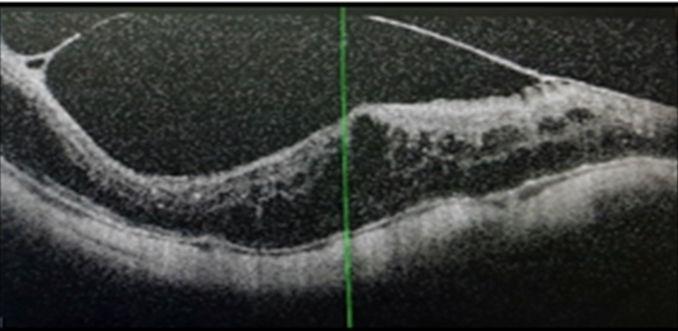

מדובר בבדיקה חדשנית אשר נמצאת בשימוש קליני בשנים האחרונות. הבדיקה מבוססת על תכנה מתקדמת אשר מבצעת 100,000 צילומים בשנייה אחת וכך מאפשרת לבחון בדיוק רב את זרימת הדם בנימים הפנימיים בעין [תמונות 5,6]. זוהי למעשה הבדיקה היחידה בגוף שמראה את בריאות הנימים הפנימיים בבדיקה שאינה פולשנית. תוצאות הבדיקה מספקות מידע חיוני על זרימת דם תקינה או חסרה, לרבות על היווצרות נימים חלשים שיכולים לדמם; על תגובת הנימים החולים לטיפולים; ועוד. הממצאים יכוונו להחלטות הטיפוליות. בדיקה זו כבר נעשית כיום במספר מחלקות עיניים בארץ ובמרפאות עיניים שונות.